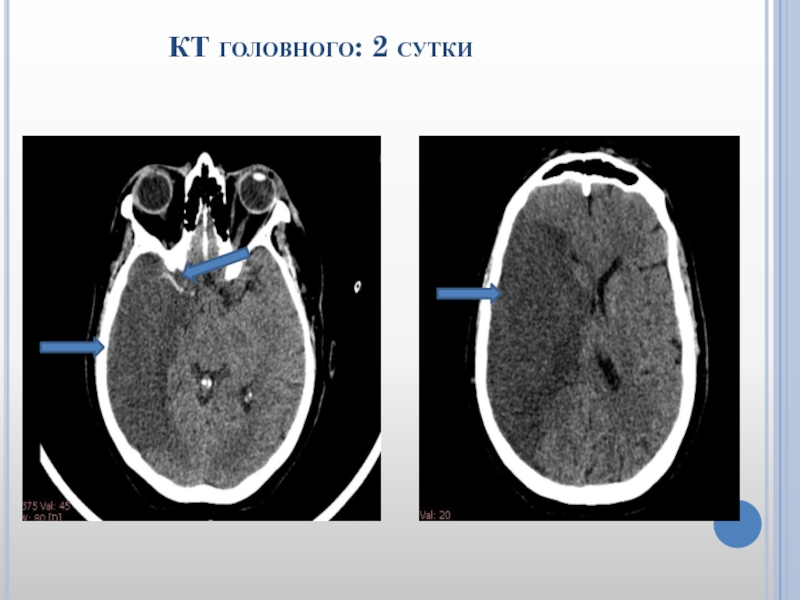

Слайд 29 КТ головного: 2 сутки

Слайд 30 КТ головного: 2 сутки

Слайд 31 Пациентке на 2 сутки выполнена декомпрессивная трепанация

черепа